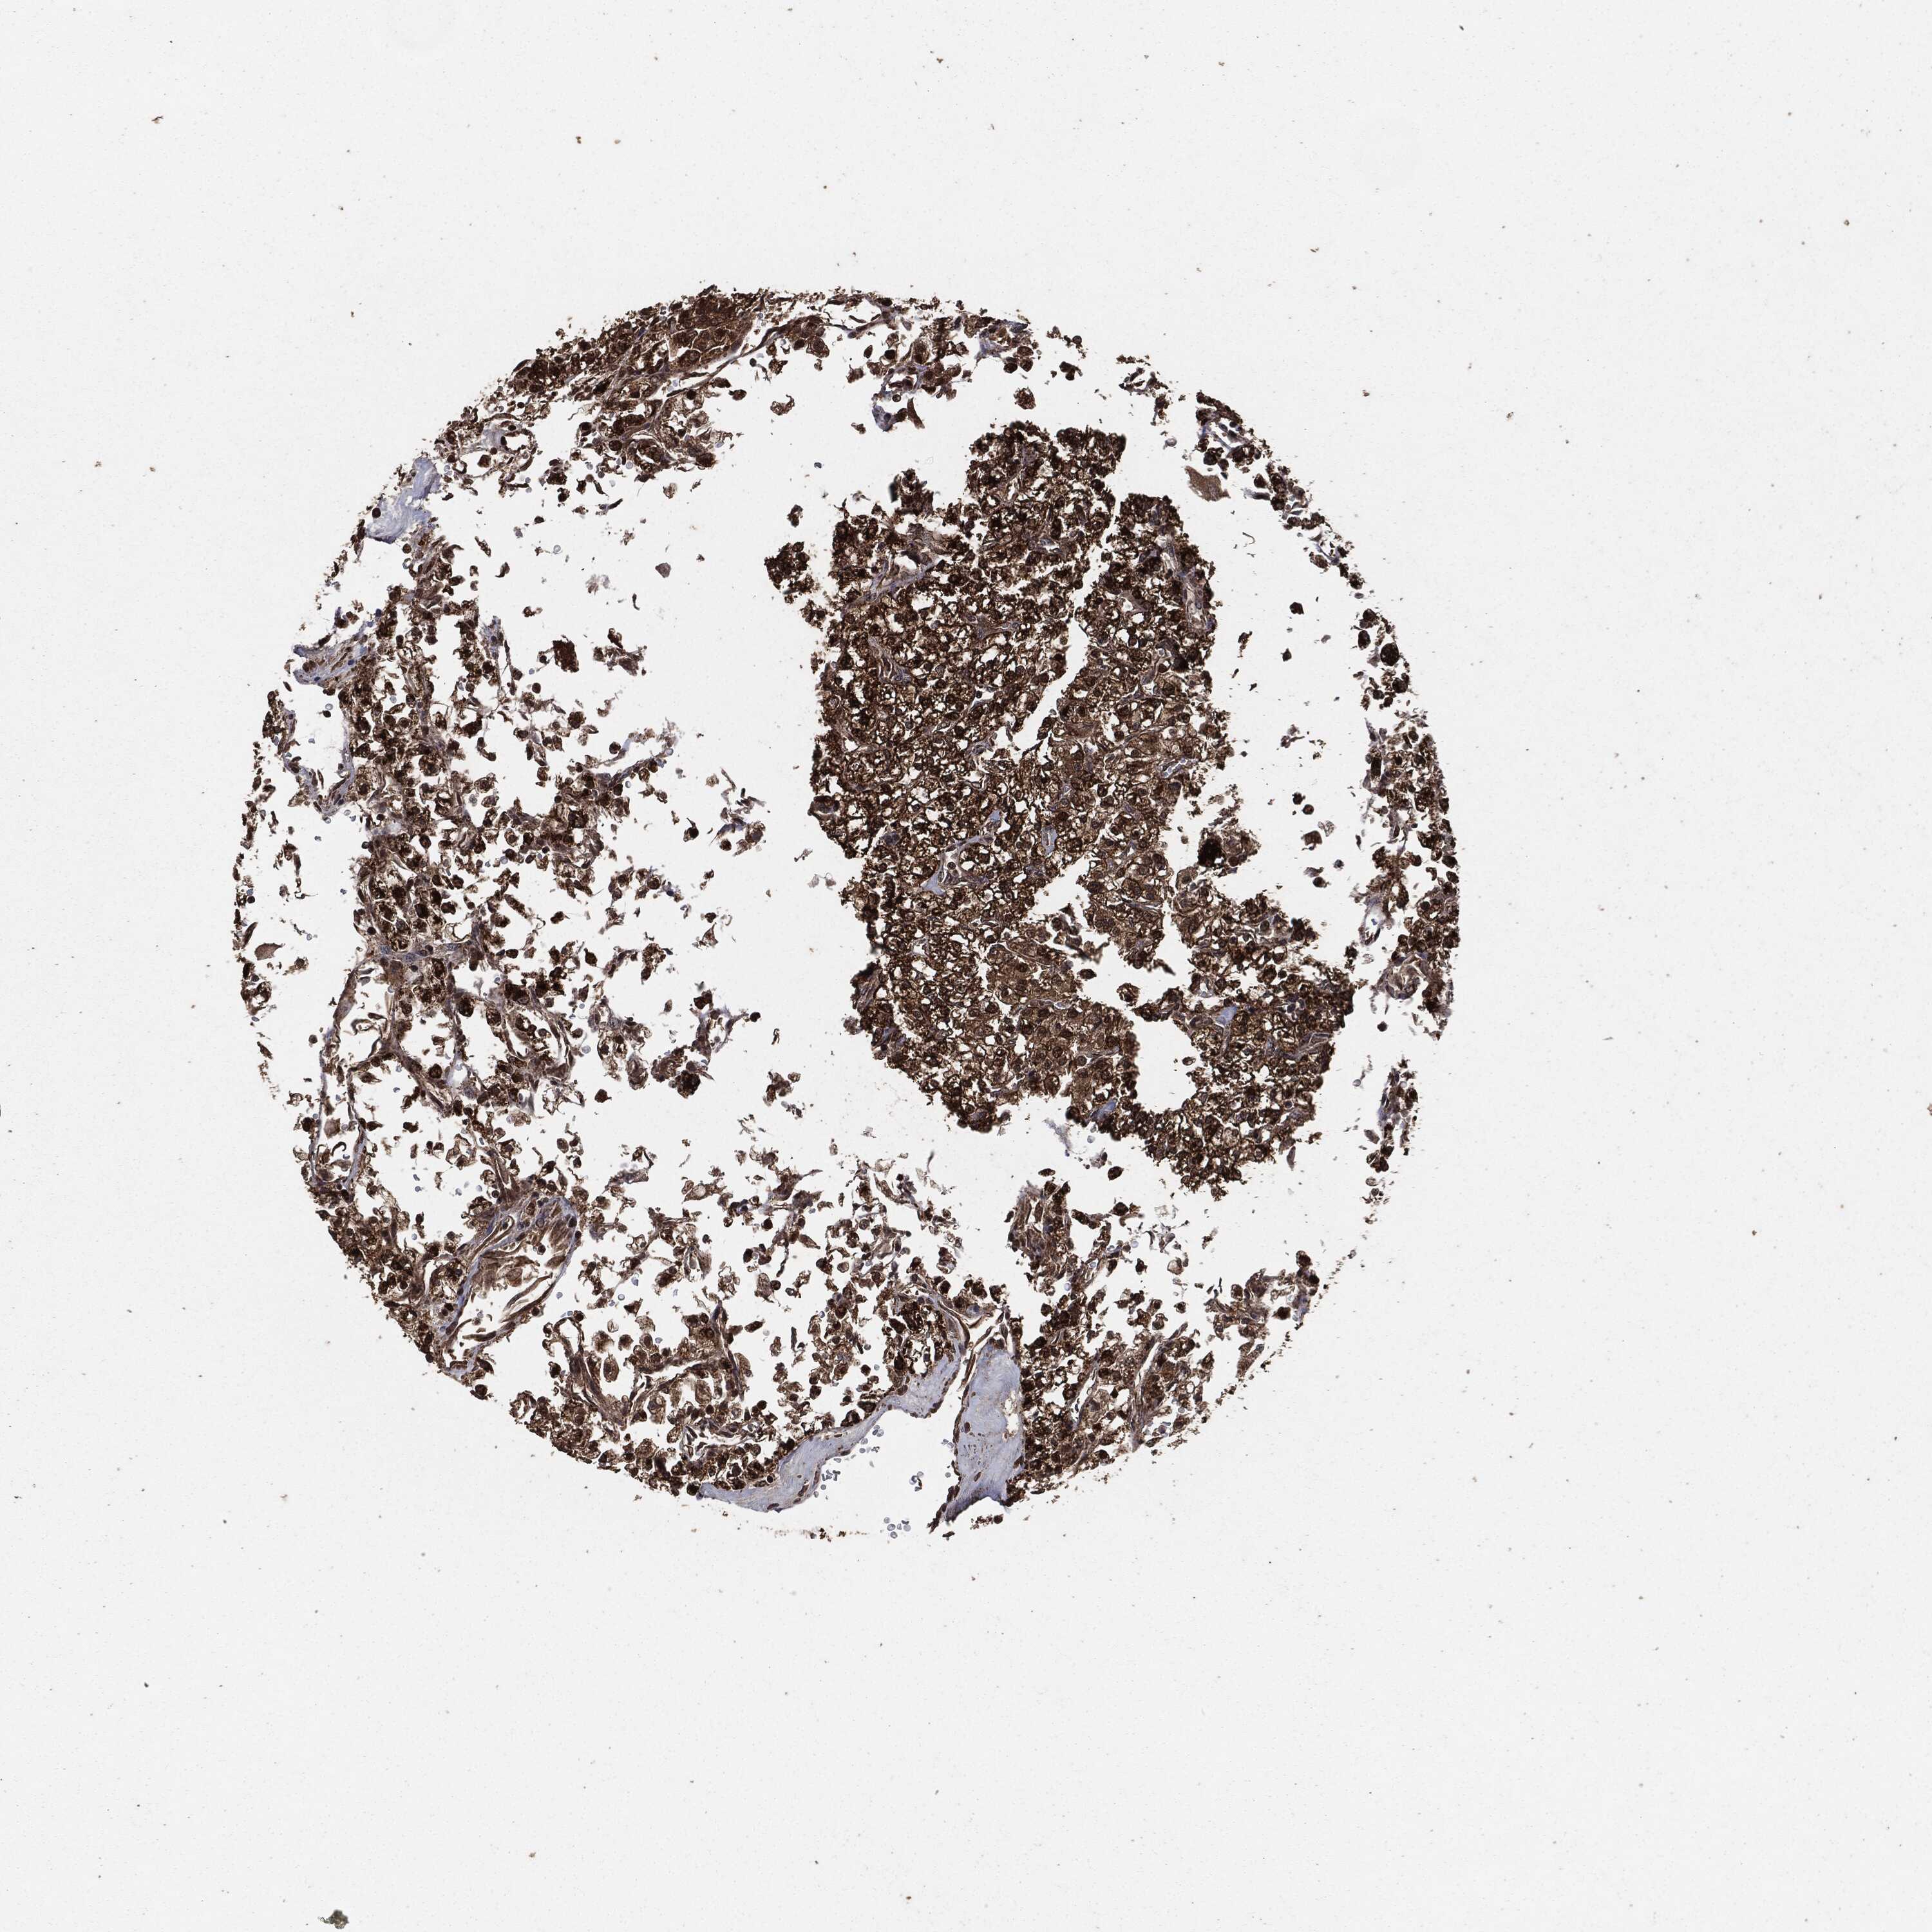

KIDNEY RENAL PAPILLARY CELL CARCINOMA (TCGA) - Interactive survival scatter ploti

The Survival Scatter plot shows the clinical status (i.e. dead or alive) for all individuals in the patient cohort, based on the same data that underlies the corresponding Kaplan-Meier plots. Patients that are alive at last time for follow-up are shown in blue and patients who have died during the study are shown in red.

The x-axis shows the expression levels (FPKM) of the investigated gene in the tumor tissue at the time of diagnosis. The y-axis shows the follow-up time after diagnosis (years). Both axes are complimented with kernel density curves demonstrating the data density over the axes. The top density plot shows the expression levels (FPKM) distribution among dead (red) and alive patients (blue). The right density plot shows the data density of the survived years of dead patients with high and low expression levels respectively, stratified using the cutoff indicated by the vertical dashed line through the Survival Scatter plot. This cutoff is automatically defined based on the FPKM cutoff that minimizes the p-score. The cutoff can be changed by dragging the vertical line or by entering a cutoff value in the square labeled "Current cut-off".

Under the Survival Scatter plot the p-score landscape (black curve; left axis) is shown together with dead median separation (red curve; right axis). Dead median separation is the difference in median mRNA expression between patients who have died with high and low expression, respectively. It is calculated as follows: median FPKM expression of dead patients with high expression - median FPKM expression of dead patients with low expression. This is intended to aid the user in visually exploring custom cutoffs and the associated p-scores and dead median separation.

Individual patient data is displayed and can be filtered by clicking on one or more of the category buttons on the top of the page. Categories describing expression level and patient information include: high, low, alive, dead, female, male and tumor stages. The scale of the x-axis can be toggled between linear and log-scale by clicking on the "x log" button. Mouse-over function shows TCGA ID, patient information and mRNA expression (FPKM) for each patient.

& Survival analysisi

Kaplan-Meier plots summarize results from analysis of correlation between mRNA expression level and patient survival. Patients were divided based on level of expression into one of the two groups "low" (under cut off) or "high" (over cut off). X-axis shows time for survival (years) and y-axis shows the probability of survival, where 1.0 corresponds to 100 percent.

EGFR is not prognostic in Kidney Renal Papillary Cell Carcinoma (TCGA)